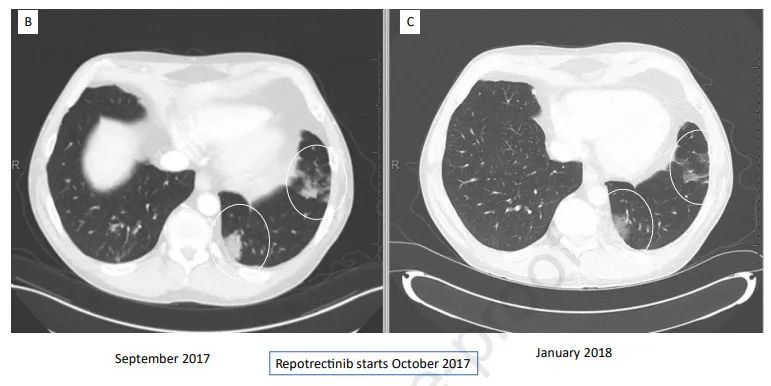

患者接受了160mg的瑞普替尼(每日一次,用药14日;之后每日两次)治疗,最初对治疗有应答(图1B和C)。在接受瑞普替尼治疗12个月后,患者出现左肺上叶的疾病进展。针对寡进展病灶进行楔形切除,然后进行NGS分析,发现了之前未检出的G2032R耐药突变,但没有其他变化。患者接受瑞普替尼治疗24个月后,疾病保持稳定,之后右肺上叶又出现了一个增大的结节。针对这一寡进展进行立体定向放射治疗(SBRT)。瑞普替尼总共治疗36个月后,患者发生整个胸部的多灶性疾病进展。基于右肺上叶进展病灶的活检组织进行NGS检测,发现一个新的L2086F突变,没有先前ROS1突变的证据。

图1B和图C:患者对瑞普替尼治疗产生应答